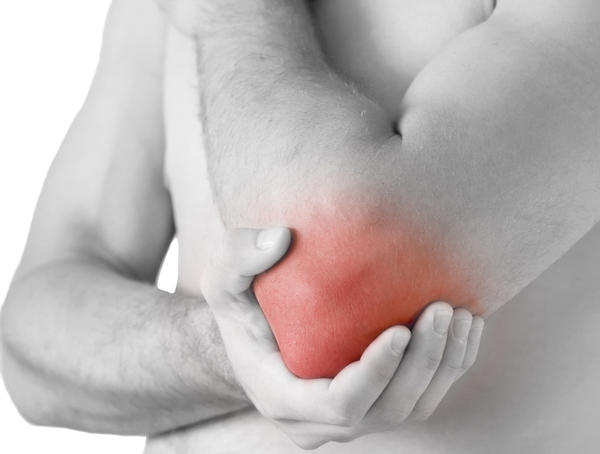

Inflamed Elbow- Bursae are thin, slippery sacs located throughout the body that act as cushions between bones and soft tissues. They contain a small amount of lubricating fluid that allows the skin to move freely over the underlying bone.

The olecranon bursa lies between the loose skin and the pointy bone at the back of the elbow called the olecranon.

Normally, the olecranon bursa is flat. If it becomes irritated or inflamed, more fluid will accumulate in the bursa and bursitis will develop.

Treatment- If your doctor suspects that bursitis is due to an infection, he or she may recommend aspirating (removing the fluid from) the bursa with a needle. This is commonly performed as an office procedure. Fluid removal helps relieve symptoms and gives your doctor a sample that can be looked at in a laboratory to identify if any bacteria are growing. This also lets your doctor know if a specific antibiotic is needed to fight the infection.